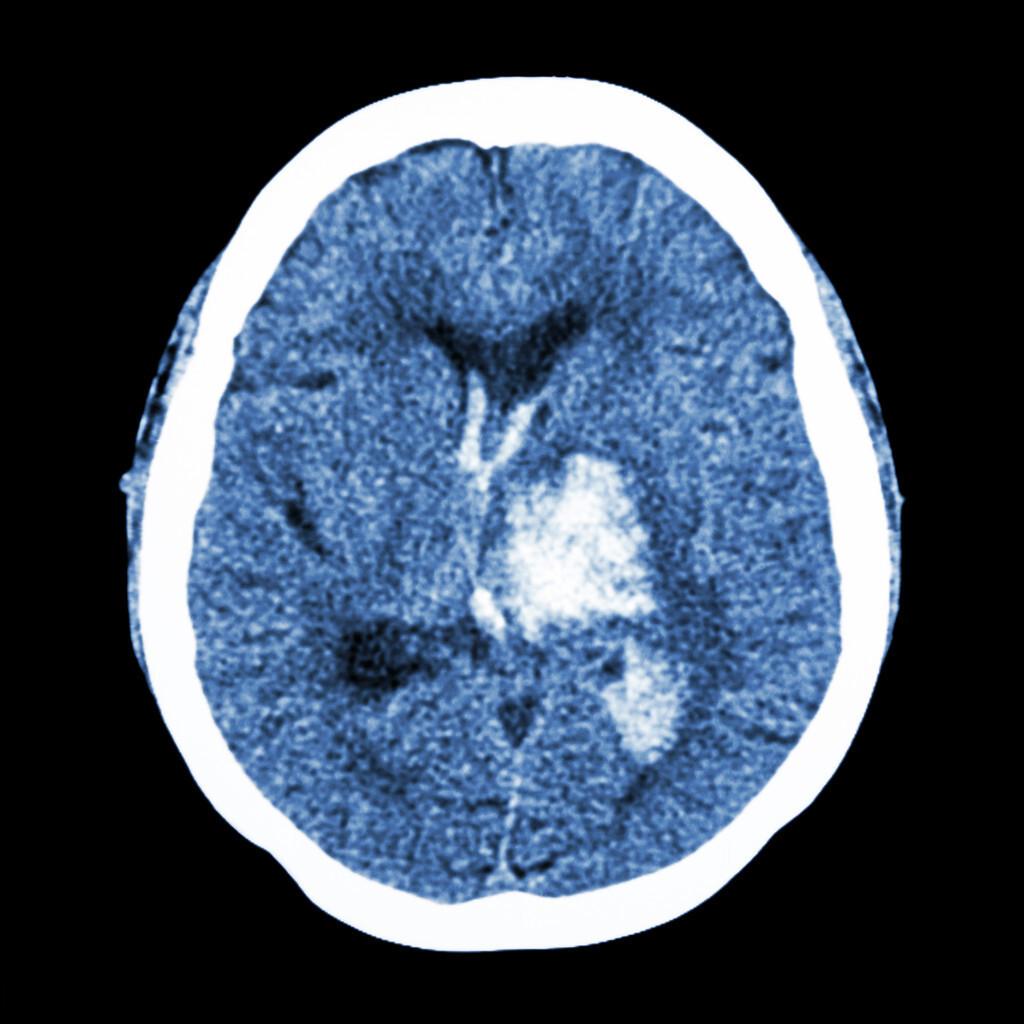

甘露醇和高渗盐水是临床上常用的两种降颅压方法,但你真的会正确使用它们吗?这两种方法各有特点,在不同情况下需要谨慎选择。

那么,在实际临床工作中,应该如何选择使用这两种方法呢?一般来说,对于颅内压升高的患者,如果存在低血压或血容量不足,可以优先考虑使用高渗盐水,因为它不仅能降低颅内压,还能增加血管内容量。而对于肾功能不全的患者,则更适合使用甘露醇。此外,对于颅脑创伤、蛛网膜下腔出血、颅内血肿、脑梗死和颅内感染等不同病因引起的颅内高压,两种方法都有应用价值。